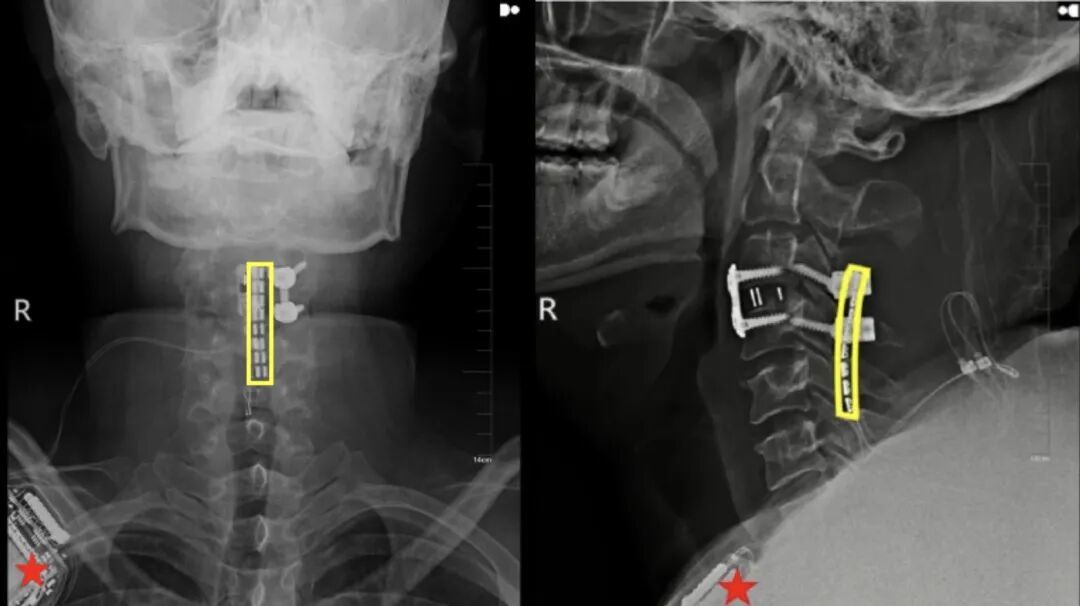

刘先生是在执行公务时不幸被车撞伤,被紧急送往吉大二院后检查发现,他的肺损伤严重,存在大量胸腔积液,同时颈三严重骨折错位,呼吸衰竭,生命垂危。

颈三骨折错位指的是第三颈椎(C3)发生了骨折且出现椎体位置异常,因涉及高位颈脊髓,是极其危重的医疗情况。“很多颈四以上损伤的患者,甚至都来不及送到医院,当场就去世了。”吴敏飞告诉“医学界”。

挽救生命是当务之急。刘先生入院后,吉大二院立即启动重伤救治绿色通道,由吴敏飞主刀完成神经减压内固定术。

值得一提的是,手术中,吴敏飞考虑到后续存在着脊髓神经接口植入的可能,同步在颈椎损伤段预留了一个“接口”。

手术非常成功,术后一个月,刘先生的恢复情况良好,生命体征保持稳定。但由于颈椎严重损伤致完全性截瘫,他的脖子以下彻底失去了运动能力和感觉,大小便失禁。